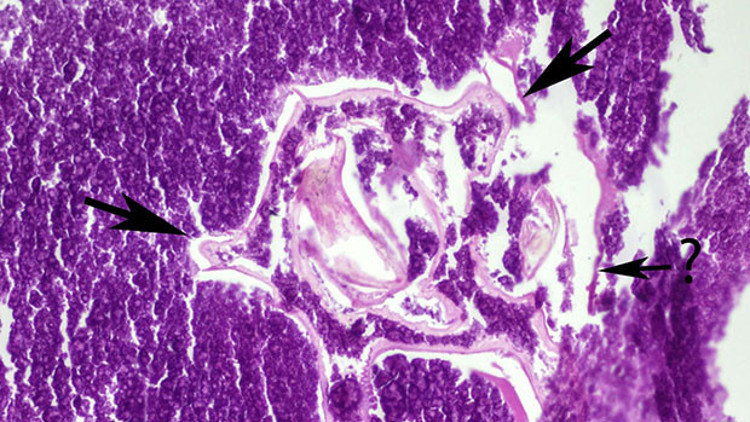

Patolojiye gönderilen tümörün mikroskobik incelemesinde, orta kısmında bir böcek olduğu belirlendi.

"Hastamızdan alınan dokunun patolojik incelemesinde tümörün orta kısmında daha önceden soluk borusuyla akciğerine kaçmış olan bir böceğin kalıntısı tespit edildi. Böceğin etrafının hücreler tarafından adeta mumyalandığı ve daha sonra çevresindeki dokunun kalınlaşmasıyla tümoral dokuya dönüştüğü belirlendi. Karşılaştığımız bu durum, özellikle akciğer tümörleri açısından tıp literatüründe karşılaşılabilecek çok ender bir durum."